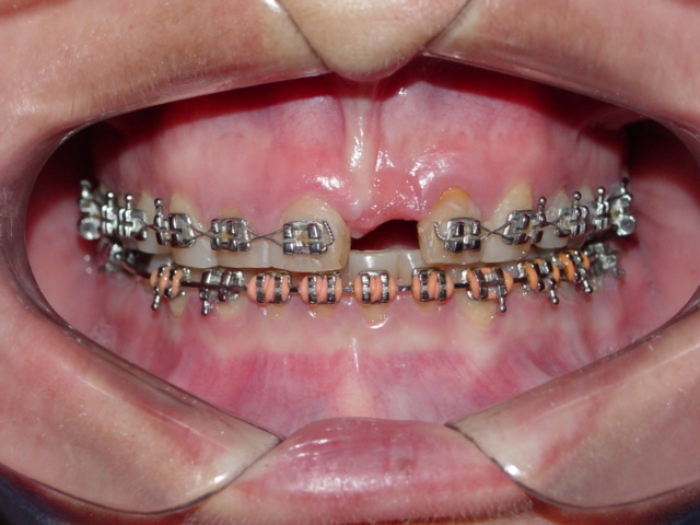

Imagens iniciais observando a ausência do incisivo central superior esquerdo